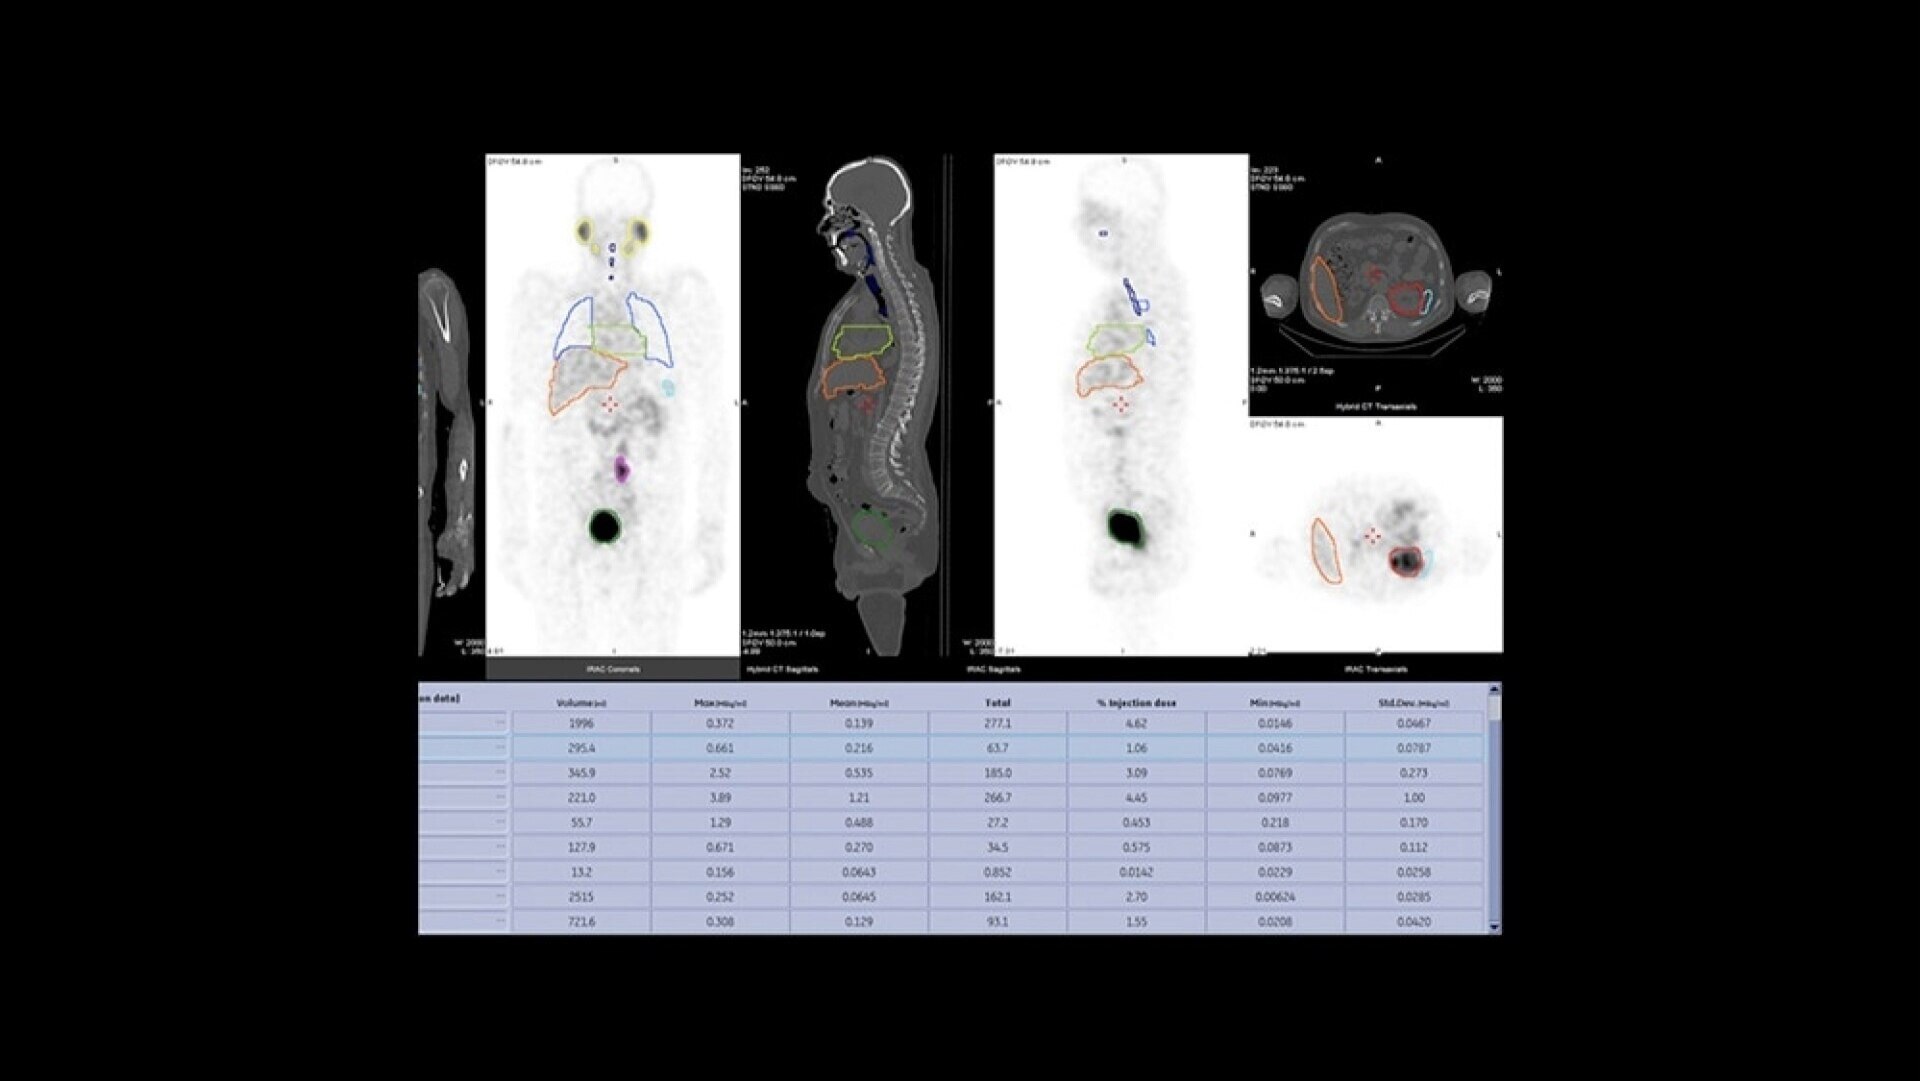

Quantitative SPECT/CT for every patient, every day

NM/CT 870 CZT is a SPECT/CT built for consistent, reproducible quantitation. Improvements to detector performance enable exceptional spatial and energy resolution. It also leverages CT-based attenuation and scatter correction along with Evolution3 image reconstruction. In addition, ever-increasing computational power enables precise camera calibration for less variation between exams.

Once your quantitative studies are acquired, SmartConsole - together with Xeleris - makes it easier to access them. Your quantitative SPECT/CT studies are automatically transferred directly to the PACS or other pre-defined DICOM destinations. An additional dataset in PET DICOM format allows you to review and evaluate images on the same devices you use to view your PET/CT studies, as adjacent information to the original SPECT/CT images.

nm-ct-870-czt-quantitative-ci-en